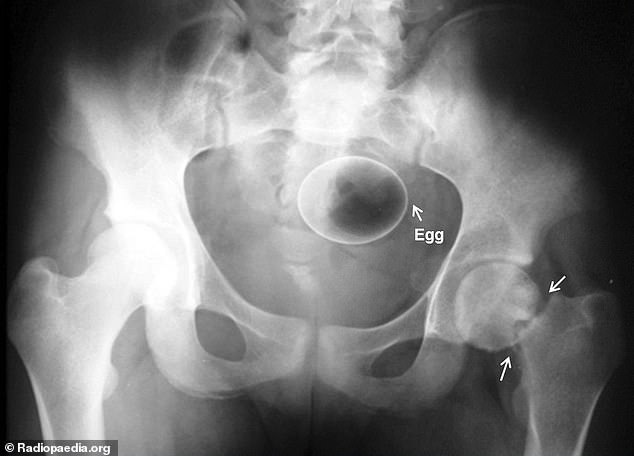

10. Ένα αυγό